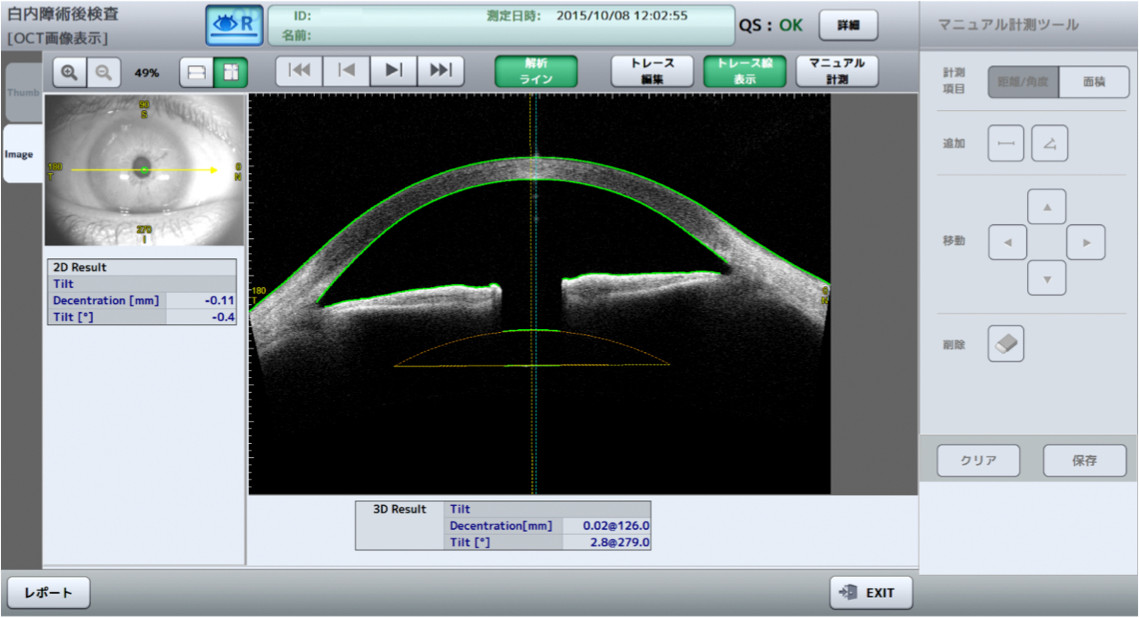

Cataract

Onze speciale Pre-operatieve cataract-applicatie begeleidt u naar een zeer goede voorbereiding op de ingreep. De screening verzamelt alle essentiële en noodzakelijke gegevens voor uw ideale IOL-keuze.